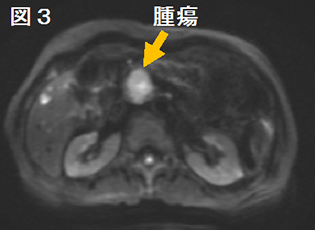

膵がんは浸潤する力が強いため、周囲の膵組織との境目がはっきりしないことが多く、CTやMRI(核磁気共鳴検査: 磁石の力で体の中を検査する方法)では判定しにくいことが多いです。膵管が詰まった場合は、流れの悪くなった膵液で膵管が拡がってきますので、それを目安に腫瘍の位置がわかることがあります。MRIでは液体を強調した画像を作ることが出来るため、膵液や胆汁を強調して膵管や胆管への影響を把握することも可能です。最近ではMRIの拡散強調画像という撮影方法によって、腫瘍の硬さから悪性度を判断する方法も行われております。また、肺や肝臓など他の臓器に膵がんが転移していないかも調べることができます。

CT画像 MRI拡散強調画像 MRCP画像 c) FDG-PET検査